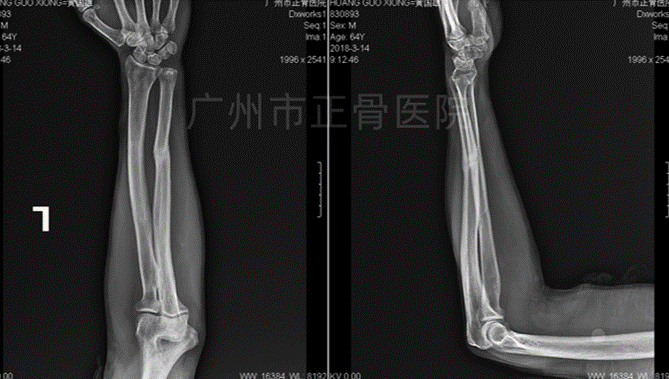

X线片检查结果:左侧桡尺骨双骨折,其中桡骨为多段骨折,位线尚可;尺骨骨折远端向下移位,向桡侧成角。

▲复位前,骨折明显成角移位

▲复位后,骨折对位对线良好